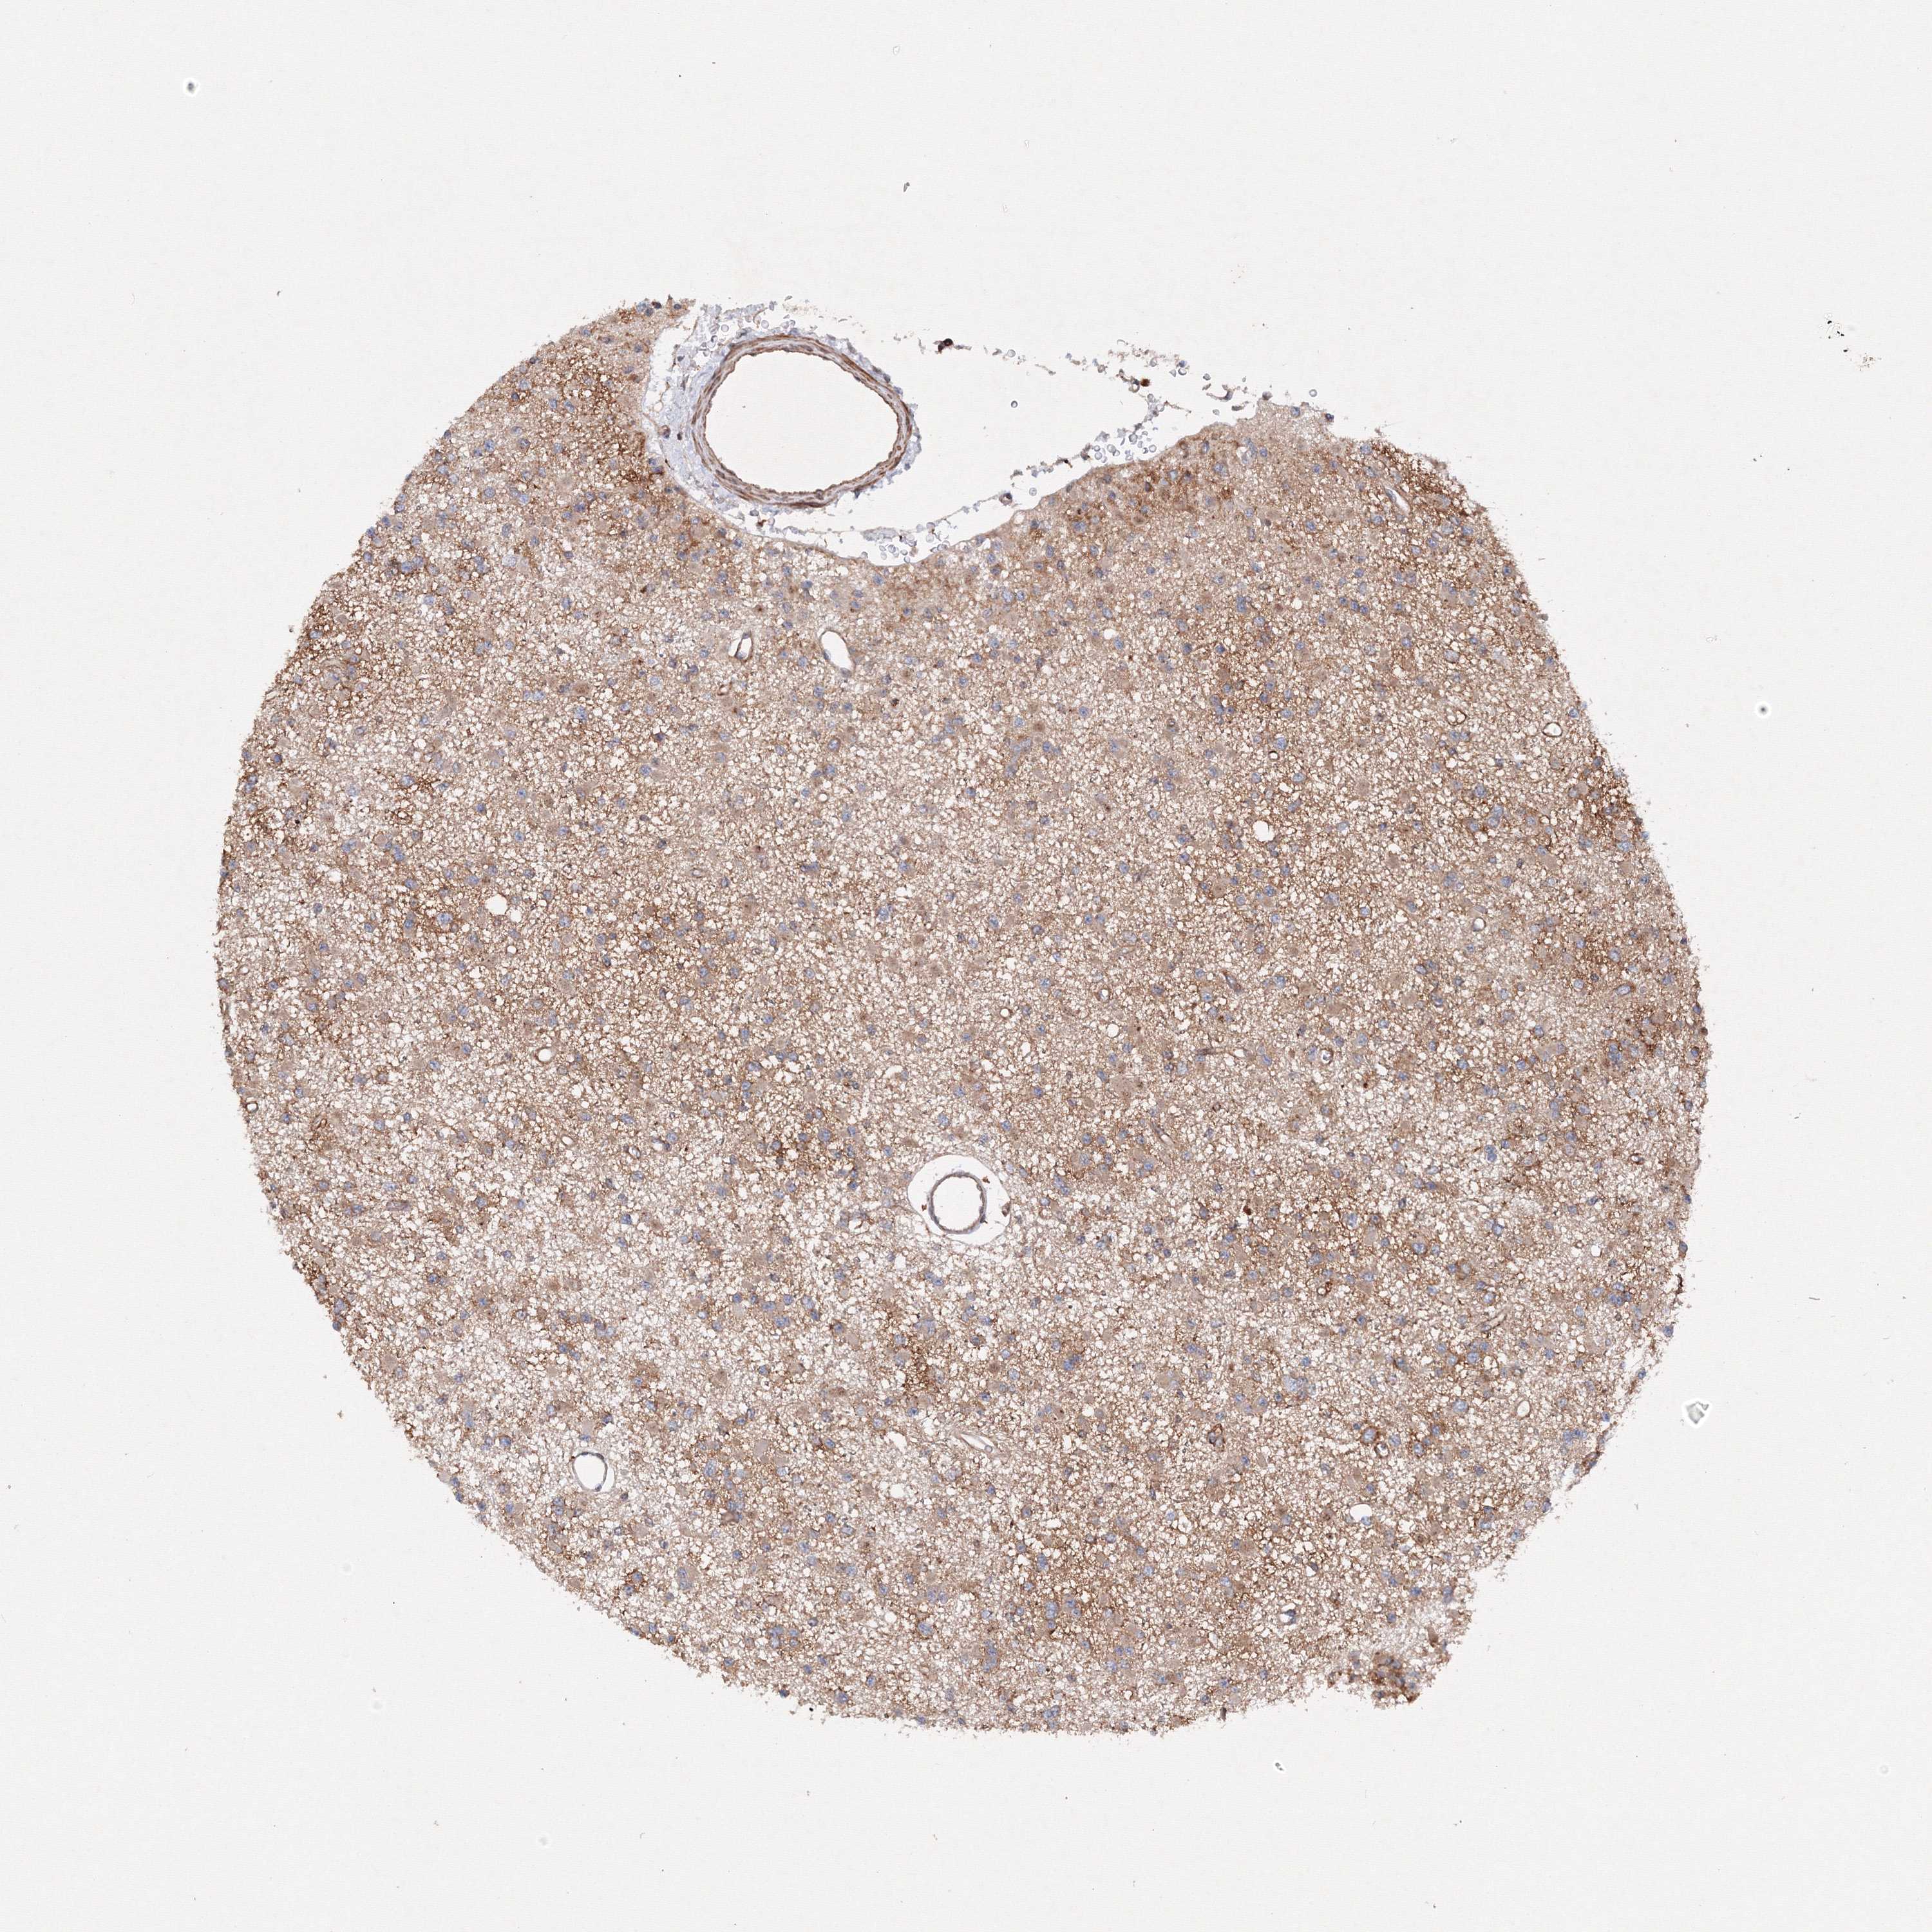

GLIOMA - Protein expressioni

A mouse-over function shows sample information and annotation data. Click on an image to view it in a full screen mode. Samples can be filtered based on level of antibody staining by selecting one or several of the following categories: high, medium, low and not detected. The assay and annotation is described here.

Note that samples used for immunohistochemistry by the Human Protein Atlas do not correspond to samples in the TCGA dataset.

Antibody stainingi

Antibody staining in the annotated cell types in the current human tissue is reported as not detected, low, medium, or high, based on conventional immunohistochemistry profiling in selected tissues. This score is based on the combination of the staining intensity and fraction of stained cells.

Each image is clickable and will lead to virtual microscopy that enables deeper exploration of all samples and also displays staining intensity scores, fraction scores and subcellular localization as well as patient and tissue information for each sample.

Antibody HPA035894

Staining

High

Medium

Low

Not detected

Intensity

Strong

Moderate

Weak

Negative

Quantity

>75%

75%-25%

<25%

None

Location

Nuclear

Cytoplasmic/membranous

Cytoplasmic/membranous,nuclear

Glioma, malignant, High grade

Glioma, malignant, Low grade

Glioblastoma, NOS